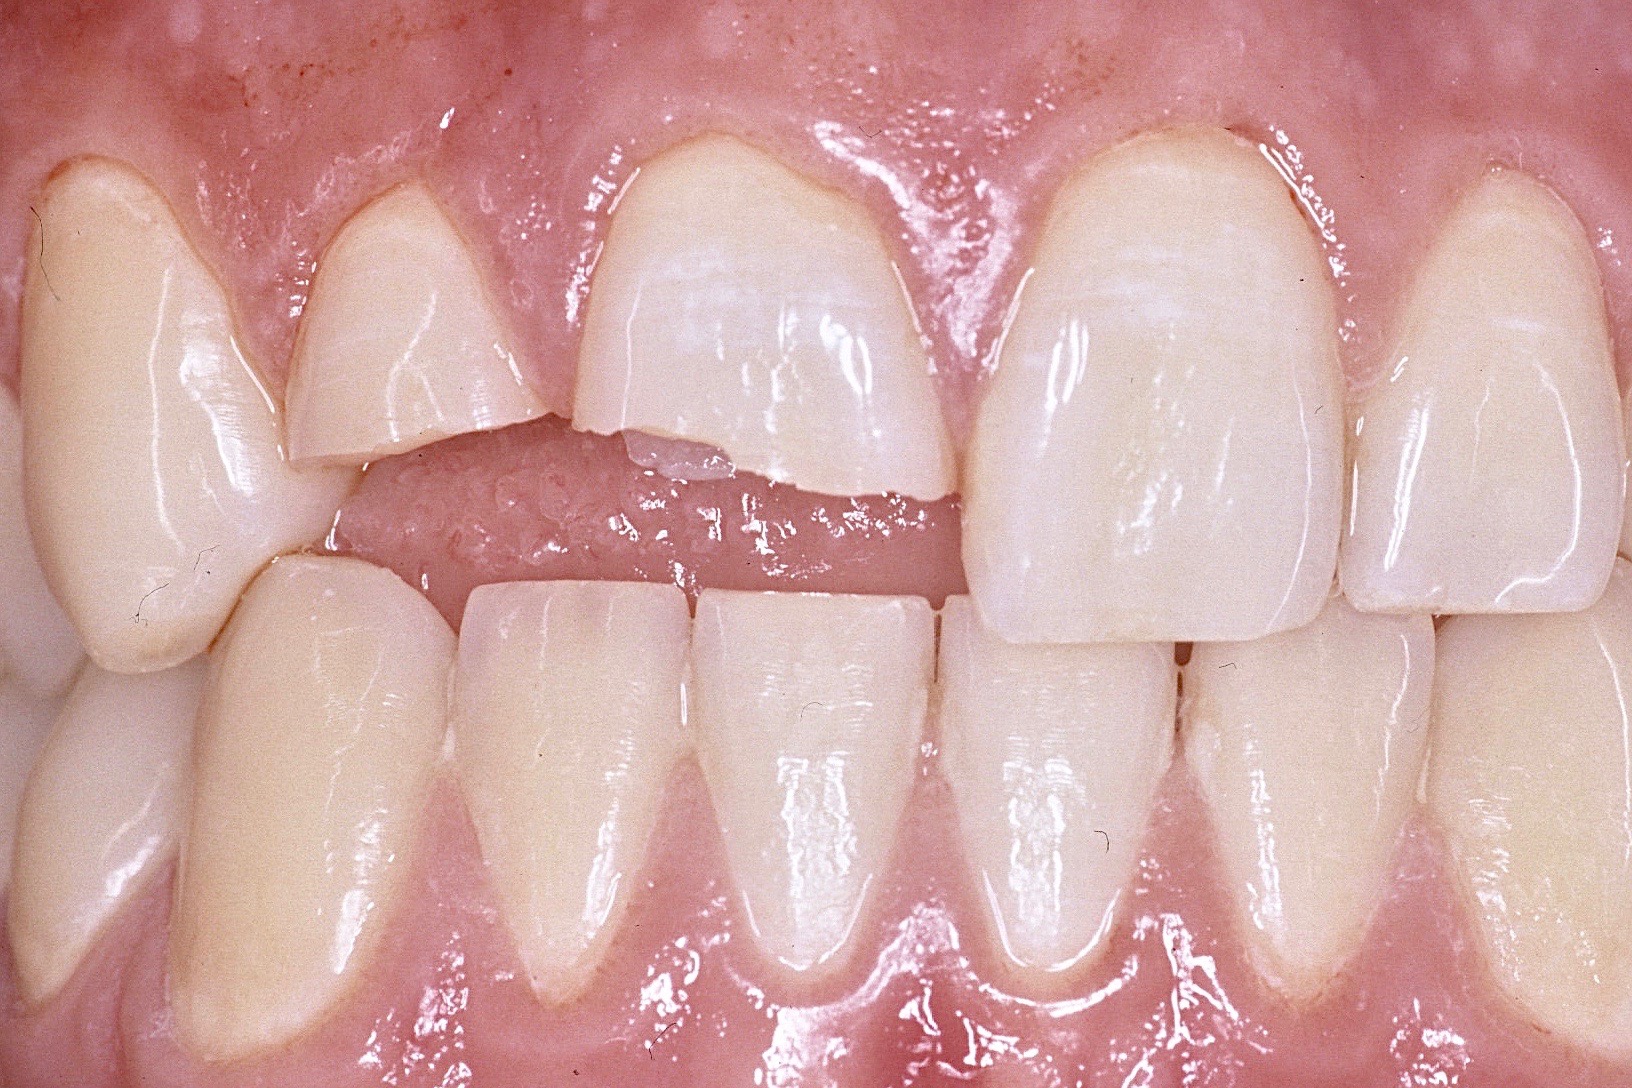

Bei der Therapie von Zahnfrakturen stehen aus endodontischer Sicht vitalerhaltende Maßnahmen im Vordergrund. Zähne mit nicht abgeschlossenem Wurzelwachstum können so ihr Wurzellängen und –dickenwachstum fortsetzen. Aus restaurativer Sicht gilt es Funktion und Ästhetik möglichst optimal wiederherzustellen. Die restaurative Versorgung von Kronen- Wurzel-Frakturen ist durch die subgingival liegenden Defektgrenzen massiv erschwert. Zur Defektdarstellung und Herstellung der biologischen Breite bieten sich verschiedene Alternativen an. In vielen Fällen ist eine kieferorthopädische oder chirurgische Extrusion ein sinnvoller Weg im Sinne der Zahnerhaltung.